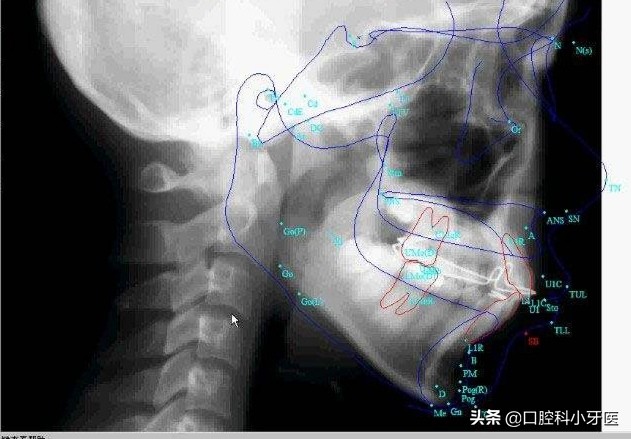

首先医生看到患者后,需要患者拍摄头影测量片,然后医师对患者进行取印模,进行牙列的分析,给出矫正的方案,对应的将牙齿治疗前的情况进行拍照记录,患者需要到口腔内科进行洁牙,将牙周的情况保持良好,个别患者可能会涉及到拔牙!